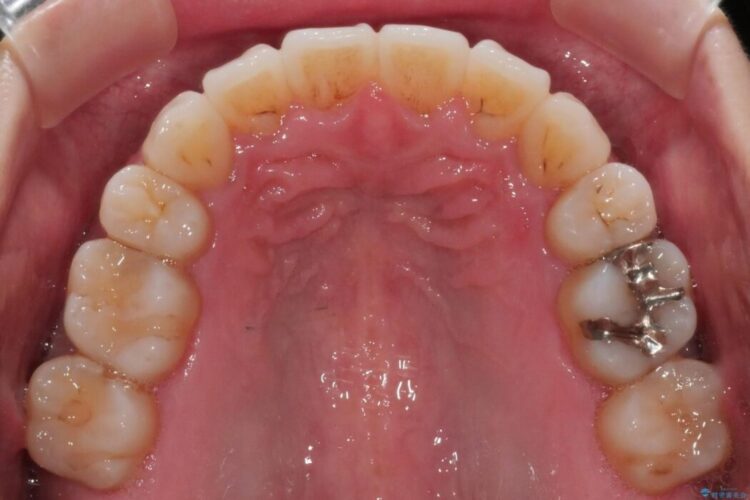

抜歯矯正後の上の前歯の後戻りが気になるとご来院された患者様です。

歯と歯の間を削るのと、歯列のU字型のアーチを僅かに外側に広げる事でスペースを作り、前歯の角度の改善をしました。

保定装置は、マウスピースと前歯の裏側を細いワイヤーで固定(ボンディングリテーナー)を併用していただいてます。